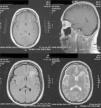

Case ReportThe patient was a 47-year-old woman diagnosed with SLE 10 years ago, with an outbreak of renal activity one year prior to admission that required treatment with mycophenolate mofetil (MMF) 3g daily, prednisone 1mg/kg with reduction to 0.5mg/kg/day, achieving disease activity remission. She was admitted with sudden onset headache, with an intensity of 9/10 on the visual analog scale, exacerbated with movement and no improvement with analgesics, accompanied by fever and nausea. Upon physical examination, she had no alterations in consciousness, impairment of higher mental functions or focal neurological data and presented negative meningeal signs. Study of the cerebrospinal fluid (CSF) showed leukocytes 27mm−3 (80% mononuclear), RBC 45mm−3, protein levels, normal CSF glucose, other tests and Gram stain were negative, IgM and IgG antibodies to cytomegalovirus and herpes virus were negative. Laboratory studies showed leukocytosis 13000cel./Mm3 with neutrophilia and monocytosis, low C3 levels with normal C4, elevated titers of anti-DNA, urinalysis with proteinuria, microhematuria and negative cylinders. The initial diagnosis was neuroinfection vs neuropsychiatric SLE activity; we began empirical treatment with ceftriaxone 2g every 12 h, vancomycin 1g every 12 h, acyclovir 600mg every 8 h, dexamethasone 8mg every 8 h. Magnetic resonance imaging (MRI) of the brain showed, on the frontal lobe, an injury consistent with a brain abscess (Fig. 1). At 48h the CSF was reported colorless, no leukocytes, erythrocytes 15, protein 39mg/dl and normal CSF glucose, PCR for M. tuberculosis was negative. After 4 days, LM growth was reported in the CSF, negative blood cultures, leading to a change in treatment ampicillin 2g intravenously every 4h for 6 weeks, with complete resolution without sequelae. A cerebral MRI after one month showed a nodular impregnation area 3mm diameter situated frontally with minimal adjacent edema. At 4 months there was evidence of the infectious process (Fig. 2).

MRI on admission: CSF spaces, cerebellum, medulla, pons, midbrain, corpus callosum and right hemisphere are normal. In the left hemisphere, at the level of the deep white matter of the frontal lobe, there is an area of hypo-hyperintense signal in T1 and T2, respectively, with an “edematous” bilobed appearance measuring approximately 17×6 mm, surrounded by vasogenic edema and that intensely permeates annularly after application of intravenous contrast. Changes are compatible with neuroinfection. Bilobed left frontal abscess.